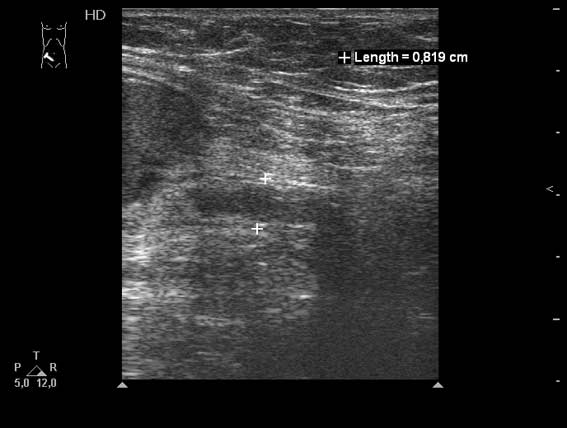

Женщина 59 лет поступила в приемное отделение БСМП с болями и пальпируемым образованием в правой подвздошной области.

О.аппендицит, аппендикулярный абсцесс. Задренирован, санирован, пациентка выписана домой.

На прошлой неделе появилась в клинике повторно для плановой аппендэктомии. При УЗИ патологии в правой подвздошой области не выявлено.